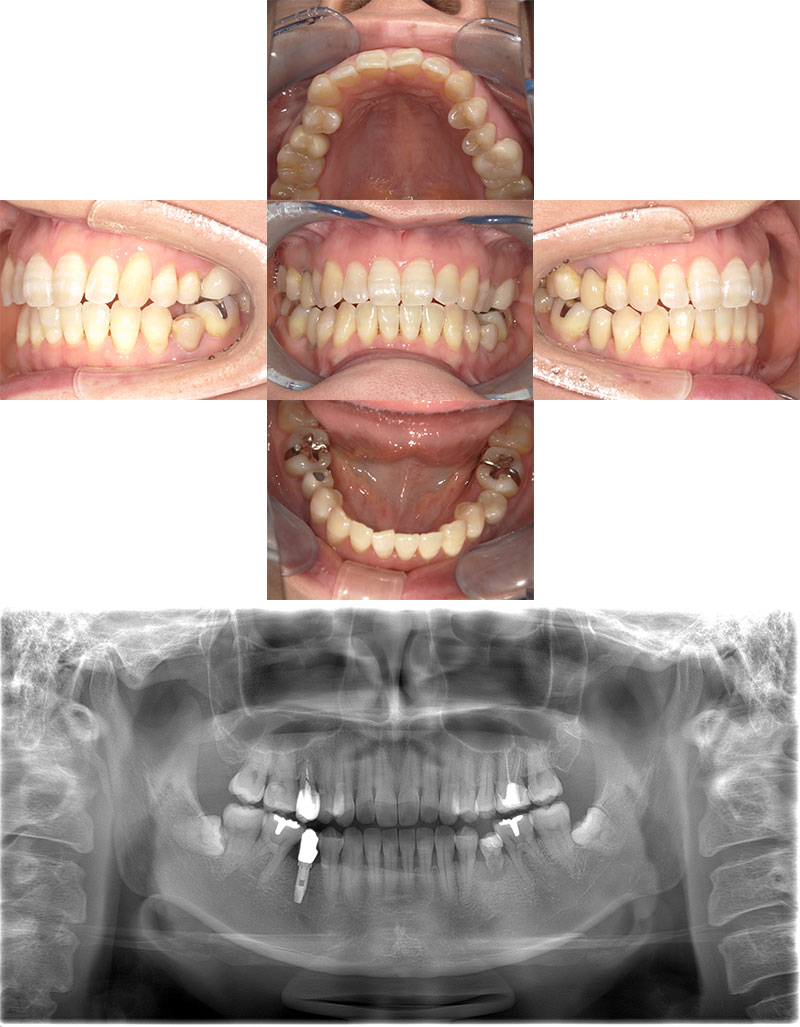

大学病院の口腔外科で培った豊富な経験と高度な技術に基づき、インプラント治療を行います。

骨が足りない場合の骨造成(GBR・サイナスリフト)や、全ての歯をインプラントで補うAll-on-4、抜歯と同時にインプラントを入れる抜歯即時埋入など、他院では難しいとされる難症例にも対応しています。

事前のCTによる精密な診査・診断を基に、安全性を最優先した計画を立てますので、まずはご相談ください。

安全性と精度を

追求したインプラント

CTとガイドで

誤差の少ない手術を実現します

事前にCTで骨の形態や神経の位置を三次元的に把握し、コンピューター上で詳細な埋入シミュレーションを行います。

その計画通りに寸分の狂いなくインプラントを埋入するため、サージカルガイドという装置を全症例で使用します。

これにより、手術の安全性と精度を飛躍的に高めます。

手術が怖い方には静脈内鎮静法も用意しています。